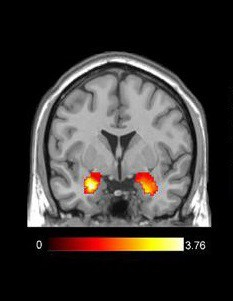

当时,一共有67个人参与了这项研究。当他们在第一种情况下品尝饮料时,研究人员使用功能性磁共振成像(fMRI)记录了他们的大脑活动。

当大脑的某个区域被激活时,血液会涌向该区域。fMRI可以捕捉这种血流的变化。它可以帮助科学家了解哪些活动可以激活大脑的哪些区域。了解哪个大脑区域会因为响应某些刺激而激活,可以让科学家弄清楚人类的行为。研究人员使用fMRI可以观察参与者在喝下不同饮料时,大脑区域被激活的情况。

标准fMRI图像。高亮部分显示杏仁核被激活。

当参与者不知道杯中饮料的品牌时,位于大脑前端的一个特定的快乐中心——“腹内侧前额叶皮质”会被点亮。大脑的这个区域对我们觉得美味的食物(例如甜味汽水)特别敏感。

另一方面,当参与者知道了饮料的品牌名称后,大脑中点亮的区域与情绪和记忆有关。当他们知道自己喝的是可口可乐时,参与者会对知道饮料的品牌名称表现出情感反应,这导致他们偏好可口可乐而不是百事可乐。不过,百事可乐并没有引起参与者的这种情感反应。